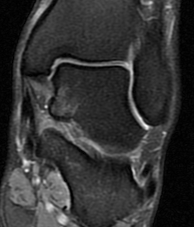

Dr. Sacco the deep portion of deltoid lig. is attenuated (non striated) and looks a bit hiperintense.